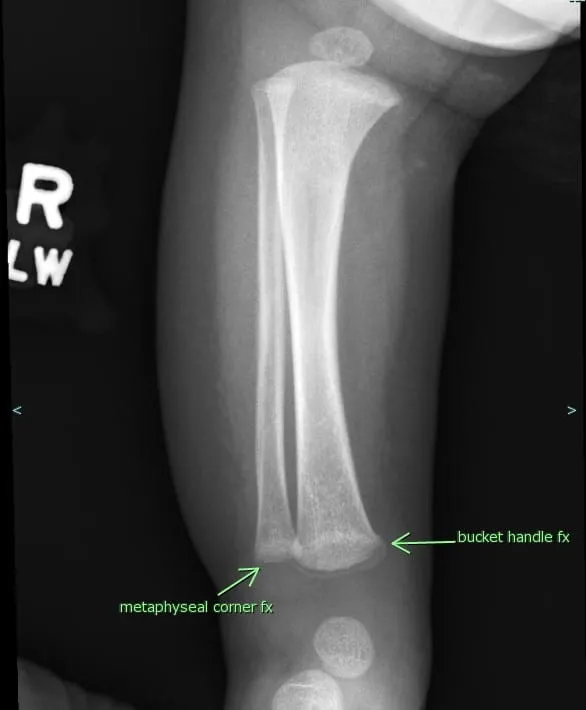

Non-Accidental Trauma - Hidden Clues

- Fractures: High-specificity patterns like metaphyseal corner fractures, posterior rib fractures, or multiple fractures in various stages of healing.